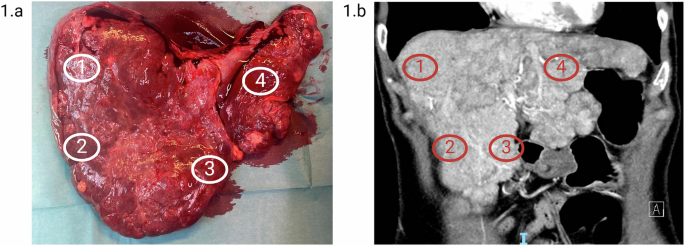

Biopsies from the hepatic vascular lesions were collected immediately after liver-extraction. A total of 8 biopsies were collected, six from objectively AVM affected areas (G142-1-6) (two biopsies each from liver segments 5, 6, and 7) and two from macroscopic normal tissue (G142-N1-2) (from liver segment 4). Segments 5 and 7 had macroscopic more severe AVM formation than segment 6. Figure 1 shows the liver after extraction and a CT scan of the liver.

a Extracted liver displaying visible arteriovenous malformations (AVMs) and multiple focal nodular hyperplasias (FNH). b Coronal contrast-enhanced CT scan in the arterial phase, showing the liver before transplantation with clearly visible intrahepatic arteries and multiple FNH lesions. Biopsies were taken from marked areas: (1) HAVM in hepatic segment 7 (sample ID: G142-3 and G142-4), (2) HAVM in hepatic segment 6 (sample ID: G142-1 and G142-2), (3) HAVM in hepatic segment 5 (sample ID: G142-5 and G142-6), and (4) macroscopic normal tissue in hepatic segment 4 (sample ID: G142-N1 and G142-N2). Created with BioRender.com.